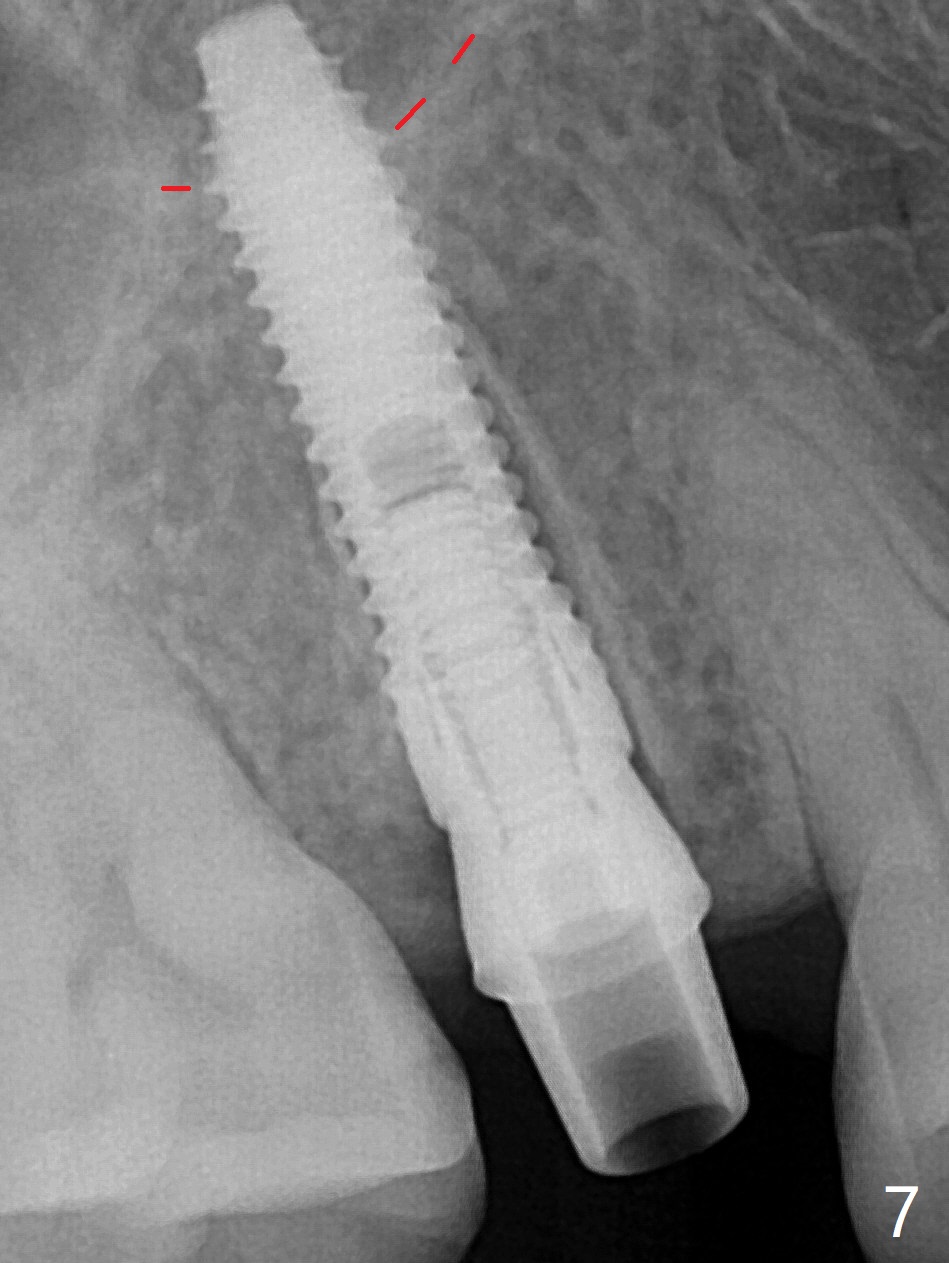

4号牙残根(图一)无创伤拔除使用一种叫做proximators牙周刀(periotomes,图二,三)。初期钻洞方位尚可(图四,五),植入3.8x15毫米植体,扭力50Ncm,修复成品基台完全就位(图六,七),植体,基台周围间隙填入骨粉(用血液调袢)后,制备基台(图八)和临时牙冠。